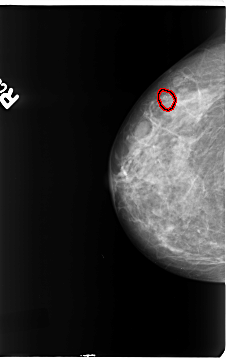

B_3145_1.RIGHT_CC

RIGHT_CC LINES 4664 PIXELS_PER_LINE 2936 BITS_PER_PIXEL 12 RESOLUTION 50 OVERLAY

FILE: B_3145_1.RIGHT_CC.OVERLAY

TOTAL_ABNORMALITIES 1

ABNORMALITY 1

LESION_TYPE CALCIFICATION TYPE PLEOMORPHIC DISTRIBUTION CLUSTERED

ASSESSMENT 4

SUBTLETY 4

PATHOLOGY BENIGN

TOTAL_OUTLINES 1

BOUNDARY